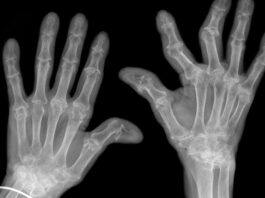

Artrosi: quanto aiuta davvero l’esercizio fisico

Un revisione sistematica coordinata dalla Bochum University of Applied Sciences, in Germania, e del Copenhagen University Hospital Bispebjerg Frederiksberg di Copenhagen, in...